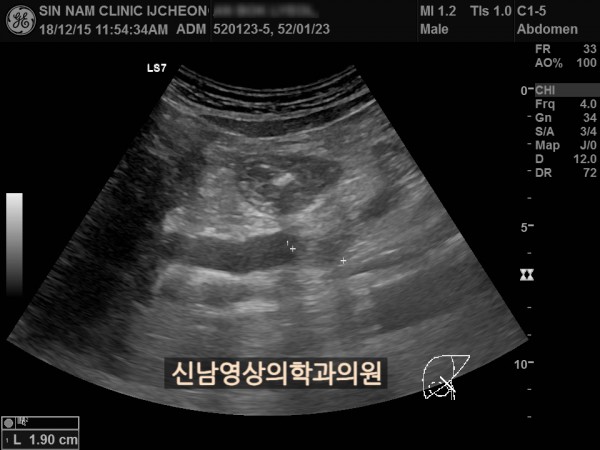

상복부 초음파 적용 사례

본 환자분은 50대 중반의 남성분으로 손가락안이 가렵다는 느낌으로 내원하셨습니다.

담도암과 담관암은 같은 질환을 지칭하는 용어로 간에서 만들어진 담즙이 십이지장으로 이동하는 통로인 담관에 발생하는 악성 종양입니다.

이 암은 간 안에 생기는 간내 담관암과 간 바깥에 생기는 간외 담관암으로 나뉘며, 가장 흔한 증상으로 통증이 없는 황달, 짙은 소변, 옅은 변, 복통, 체중 감소, 소양증 등이 나타날 수 있습니다.

![]()